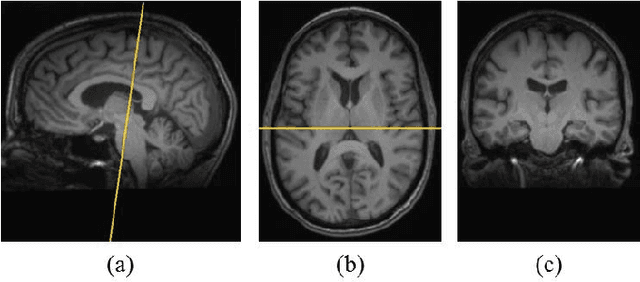

Abstract:Texture analysis is a well-known research topic in computer vision and image processing and has many applications. Gradient-based texture methods have become popular in classification problems. For the first time we extend a well-known gradient-based method, Co-occurrence Histograms of Oriented Gradients (CoHOG) to extract texture features from 2D Magnetic Resonance Images (MRI). Unlike the original CoHOG method, we use the whole image instead of sub-regions for feature calculation. Also, we use a larger neighborhood size. Gradient orientations of the image pixels are calculated using Sobel, Gaussian Derivative (GD) and Local Frequency Descriptor Gradient (LFDG) operators. The extracted feature vector size is very large and classification using a large number of similar features does not provide the best results. In our proposed method, for the first time to our best knowledge, only a minimum number of significant features are selected using area under the receiver operator characteristic (ROC) curve (AUC) thresholds with <= 0.01. In this paper, we apply the proposed method to classify Amyotrophic Lateral Sclerosis (ALS) patients from the controls. It is observed that selected texture features from downsampled images are significantly different between patients and controls. These features are used in a linear support vector machine (SVM) classifier to determine the classification accuracy. Optimal sensitivity and specificity are also calculated. Three different cohort datasets are used in the experiments. The performance of the proposed method using three gradient operators and two different neighborhood sizes is analyzed. Region based analysis is performed to demonstrate that significant changes between patients and controls are limited to the motor cortex.